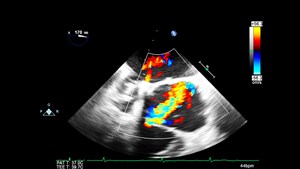

Most research has centered on transthoracic echocardiogram use (TTE). However, more emergency departments are now implementing point-of-care transesophageal echocardiogram (TEE) utilization in cardiac...